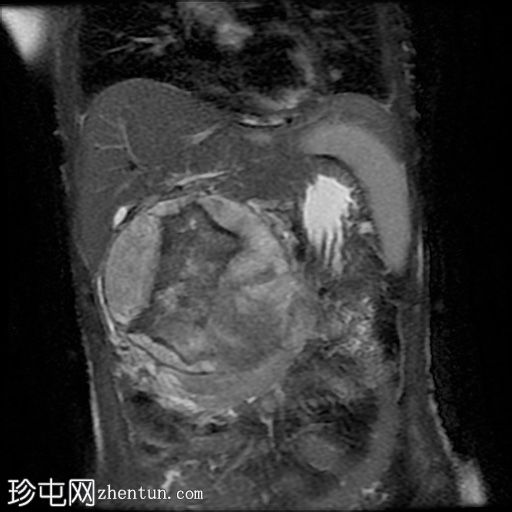

MRI

冠状位

5.jpg

病灶在T2加权像上呈不均匀高信号,内部区域信号强度不一。

MRCP显示胆总管正常,无胆管扩张或梗阻征象。

主胰管未见,可能由于肿块压迫/取代所致。